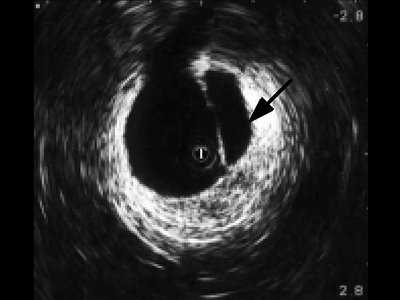

При интрауретральной ультрасонографии в неизмененных отделах мужской уретры по мере проведения датчика мы определяли головку полового члена, губчатое тело, кавернозные тела с окружающими их оболочками, сосуды. В более широком луковичном отделе регистрировались спонгиозная ткань с более тонкой стенкой и прикрепляющимися к ней мышцами (рис. 2).

Рис. 2. Эхограмма нормального луковичного отдела уретры, Т - трансдуктор.